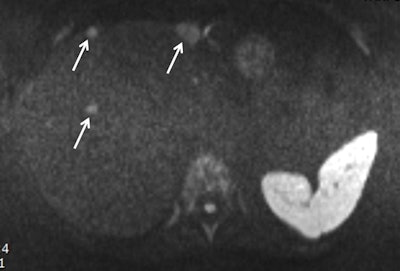

Obtained during a short protocol, this diffusion-weighted image shows a patient with conspicuous liver metastasis. The lesions are marked by arrows. Image courtesy of Dr. Thomas Lauenstein.

Obtained during a short protocol, this diffusion-weighted image shows a patient with conspicuous liver metastasis. The lesions are marked by arrows. Image courtesy of Dr. Thomas Lauenstein.During his presentation, he plans to provide a brief overview of available hardware, as well as physicist "tricks" for making single sequences faster. He will also cover how to use time more efficiently to maximize the data acquired.

One cornerstone of conventional liver MRI is delayed contrast-enhanced (CE) imaging. In a conventional protocol, acquisition of these sequences takes 15 seconds, which can be reduced to three to five seconds. The extra time gained between delay points should be used to acquire other data, such as T2-weighted imaging or diffusion-weighted imaging (DWI), which conventionally is done before or after CE sequences.

DWI is another useful MRI technique for liver imaging. However, 20% to 30% of radiologists don't include it because they don't understand its benefits, Lauenstein noted.

"DWI has a two-minute acquisition time and provides similar information to T2-weighted imaging, meaning you can skip some T2 sequences," he said. "Importantly, DWI is an all-in-one sequence which provides different information."

He suggested that in a 10-minute protocol, all CE sequences could be avoided. DWI, T2, and T1 sequences should be prioritized instead. He also highlighted some of the pitfalls of the shorter MRI protocol for liver questions: While sensitivity remains high for any clinically relevant data, there will be some loss of specificity. When results from the short protocol are abnormal, the MRI scan will need to be repeated with standard sequences. This begs the question: Who should receive the short protocols and who gets the longer ones?